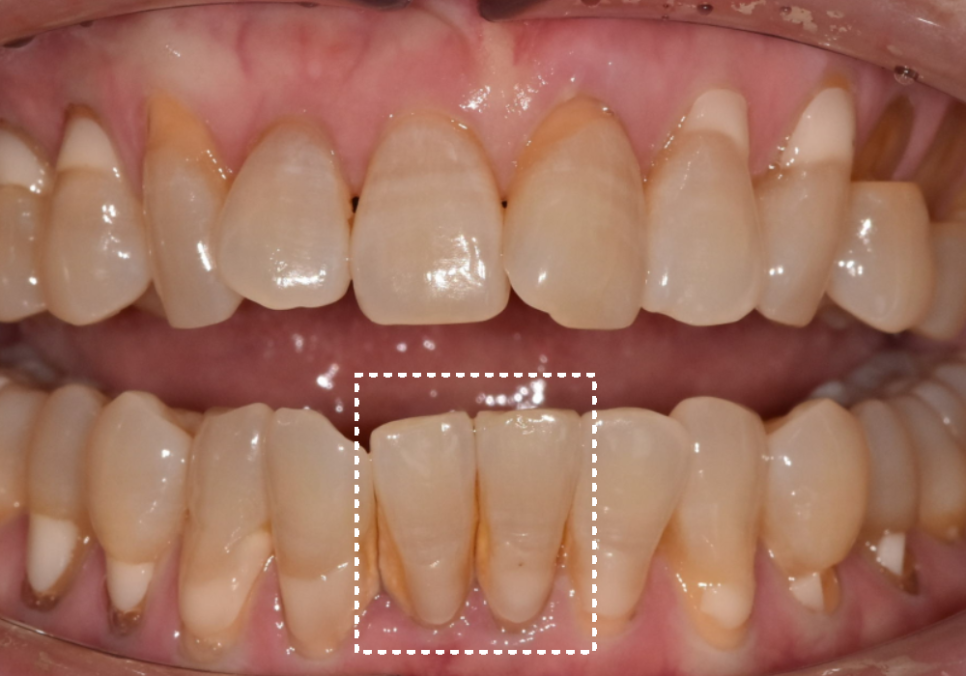

얼마 전 저희 치과를 찾으신 환자분의 사례예요.

아래 앞니가 심하게 흔들려서 내원하셨는데요~

입안을 살펴보니 아래 앞니에

두꺼운 치석이 층층이 쌓여있었습니다.